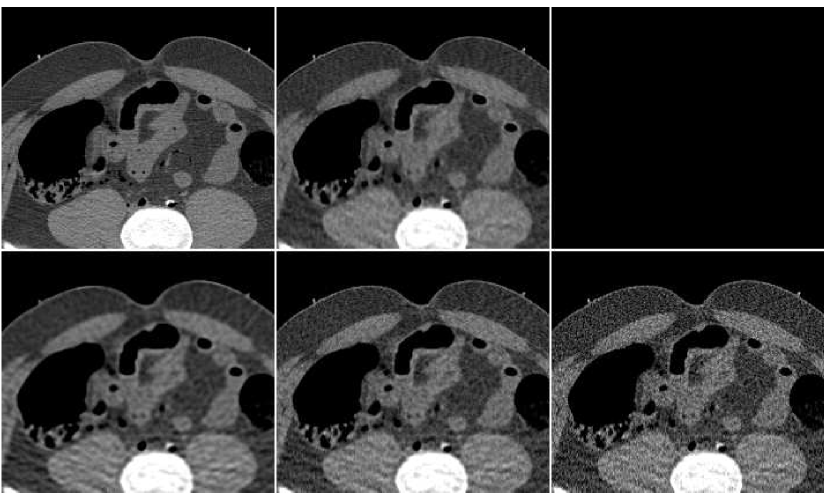

In Figure 10 we display the fusion result along with individual PWLS reconstructions, used in the fusion process. The lower part of the figure contains the absolute-valued error images. The fusion result has a higher visual quality than any of the three underlying images. Comparing to those images, the noise level in the fusion image is the lowest, and the tissue texture is closer to the original. The sharpness is the same as in the lower middle PWLS image. The SNR values (stated in the Figure) also point to the improvement in quality. The SSIM of the fusion image is , while the sequence of PWLS results have the SSIM values of (corresponding to the lower row of Figure 10, left to right). A reconstruction of an additional test image is displayed in Figure 11. The effect of the fusion observed here is similar to the one in the previous reconstruction. We conclude that the ANN-based fusion can contribute also to the iterative reconstruction, without requiring any additional iterations; the computational cost of the fusion, exercised after the reconstruction, is lower by an order of magnitude than that of the iterative process.